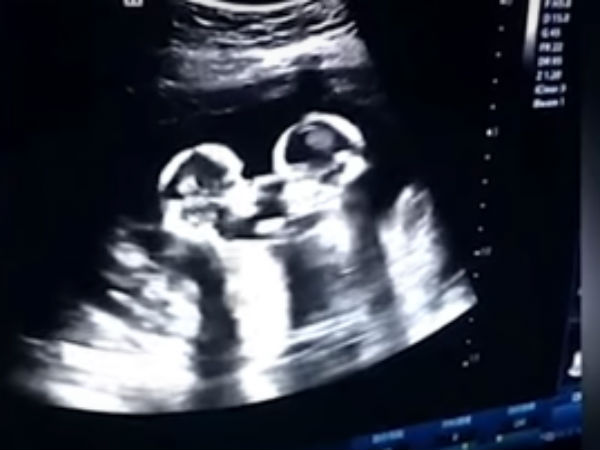

இந்நிலையில், நிறைமாத கர்ப்பிணியாக இவர் இருந்தபோது ஆஸ்பத்திரிக்கு செக்-அப்புக்காக சென்றிருக்கிறார். அங்கு அவருக்கு ஸ்கேன் செய்து பார்க்கப்பட்டது.

அப்போது கருப்பையில் இருந்த இரண்டு குந்தைகளும் சண்டை போட்டு கொண்டு விளையாடி உள்ளன. முழு கரு வளர்ந்திருந்த நிலையில் குழந்தையின் உருவம் கர்ப்பப்பையில் தெளிவாக தெரிகிறது.

குழந்தைகளின் இரு மண்டைகளும் முட்டிக் கொள்வதும், மோதிக் கொள்வதும், சில சமயம் கைகளால் தள்ளி கொள்வதும் என ஒரே சண்டையாக இருக்கிறது. இது சண்டையா, விளையாட்டா, அல்லது விளையாட்டுக்கு சண்டையா என தெரியவில்லை. இதை பார்த்ததும் குழந்தைகளின் பெற்றோருக்கு சந்தோஷம் தாங்கவில்லை.